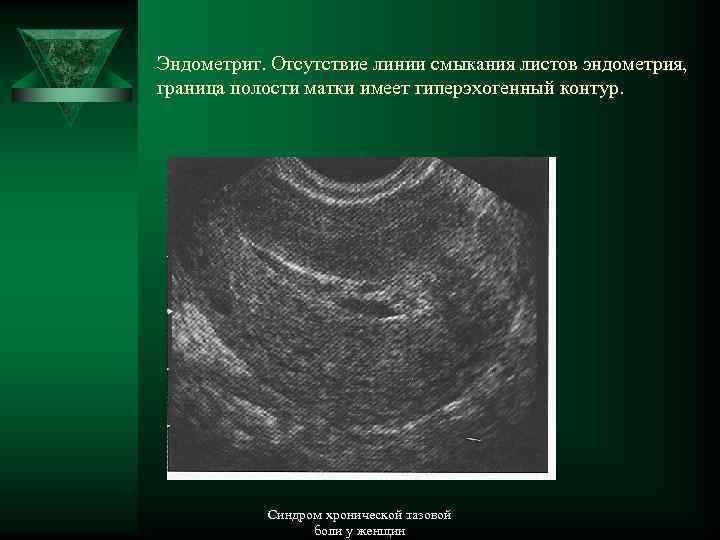

Медицинская диагностика: Гиперплазия эндометрия на УЗИ